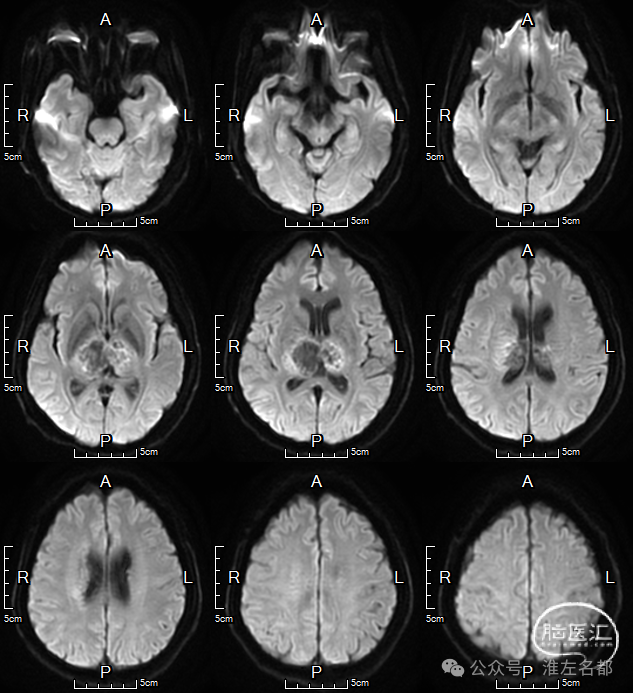

三维黑血高分辨T1

三维黑血高分辨T1平扫(上图)和增强(下图):右侧乙状窦慢性血栓,平扫呈等低信号,并显著强化。

三维黑血高分辨T1平扫(上图)和增强(下图):右侧横窦慢性血栓。

三维黑血高分辨T1平扫(上图)和增强(下图):上矢状窦慢性血栓;直窦内新进血栓(急性血栓等低信号,或亚急性血栓高信号,无强化)。

三维黑血高分辨T1平扫(上图)和增强(下图):左侧横窦发育细小。

三维黑血高分辨T1平扫(上图)和增强(下图):左侧乙状窦局部未发育。